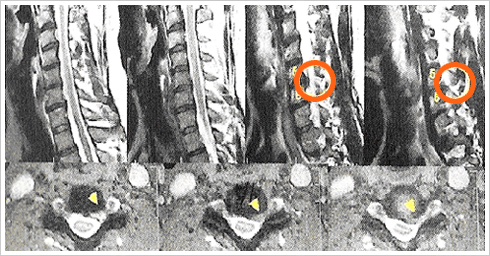

경추 추간판 탈출이라고도 하는 목디스크는

위와 같이 서서히 진행되는데, 이유는 목에 무리한 무게가 실린다면 저렇게 터져버리는 일이 빈번함.

위와 같이 디스크가 터져버린다면 수술로 고치기도 힘들어진다.